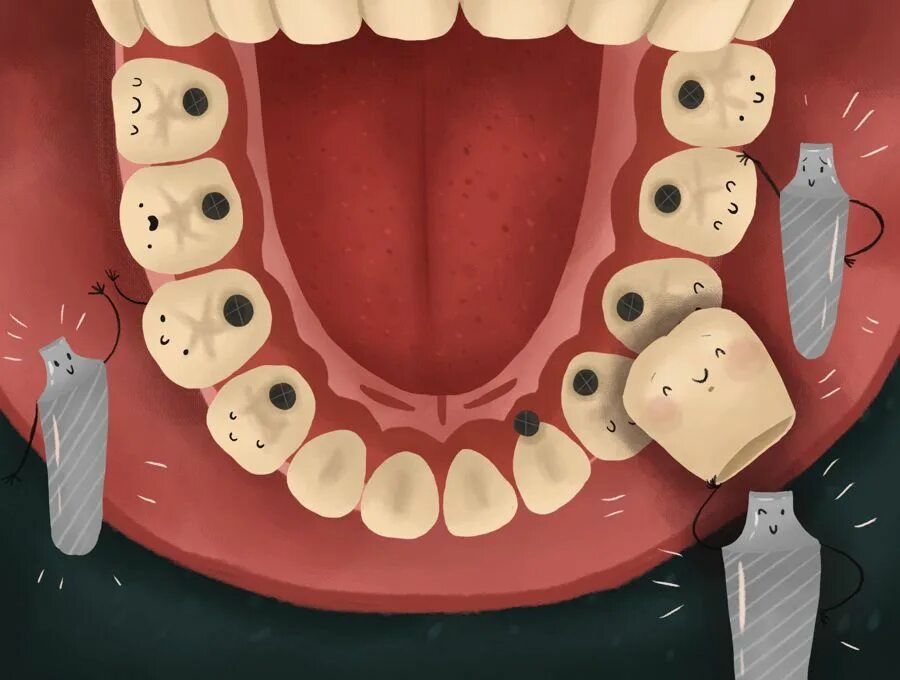

Поставить 4 зуба